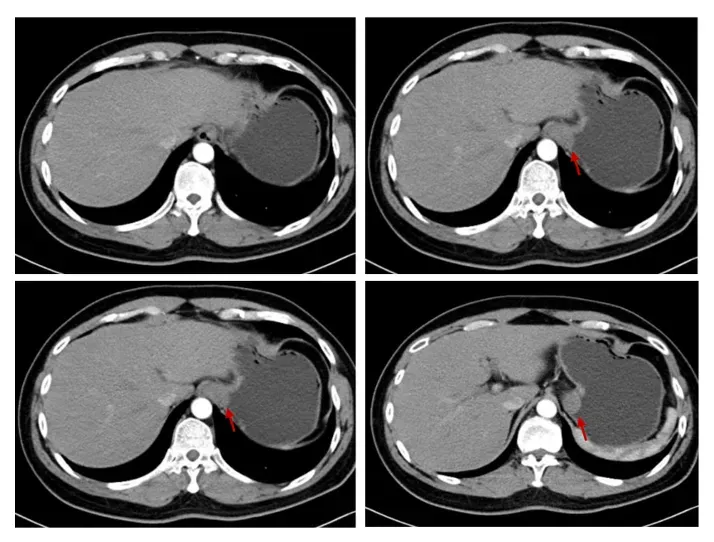

患者为38岁男性,因“反复黑便伴头晕1月”前来就诊。病程中查血红蛋白最低降至90g/L。胃镜及相关影像学检查显示:胃底贲门区可见一约4cm大小的肿物,伴有溃疡及出血。综合辅助检查考虑该患者诊断为胃间质瘤可能性大。

▲术前增强CT影像:红色箭头标注为胃底近贲门后壁肿物